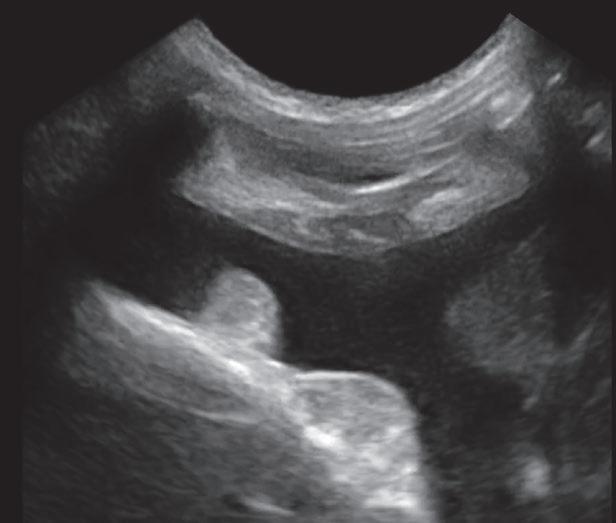

La responsabilidad de los artículos, reportajes, comunicados, etc. recae exclusivamente sobre sus autores. El editor sólo se responsabiliza de sus artículos o editoriales. La ciencia veterinaria está sometida a constantes cambios. Así pues es responsabilidad ineludible del veterinario clínico, basándose en su experiencia profesional, el correcto diagnóstico de los problemas y su tratamiento. Ni el editor, ni los autores asumen responsabilidad alguna por los daños y perjuicios, que pudieran generarse, cualquiera que sea su naturaleza, como consecuencia del uso de los datos e información contenidos en esta revista. De acuerdo con la normativa vigente en materia de protección de datos Grupo Asís Biomedia, SL., es responsable del tratamiento de sus datos personales con la finalidad de enviarle comunicaciones postales de nuestras revistas especializadas, así como otras comunicaciones comerciales o informativas relativas a nuestras actividades, publicaciones y servicios, o de terceros que puedan resultar de su interés en base a su consentimiento. Para ello, Grupo Asís podrá ceder sus datos a terceros proveedores de servicios de mensajería. Podrá revocar su consentimiento, así como ejercer sus derechos de acceso, rectificación, supresión, oposición, limitación y portabilidad enviando un correo electrónico a protecciondatos@grupoasis.com, o una comunicación escrita a Grupo Asís en Centro Empresarial El Trovador, planta 8, oficina I, Plaza Antonio Beltrán Martínez 1, 50002, Zaragoza (España), aportando fotocopia de su DNI o documento identificativo sustitutorio e identificándose como suscriptor de la revista. Asimismo, si considera que sus datos han sido tratados de forma inadecuada,